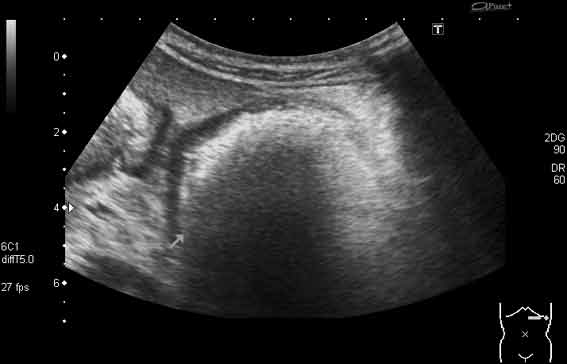

УЗИ, трихобезоар желудка. Gastric trichobesoar, ultrasonography.

Наблюдение наших коллег, работающих в педиатрии (valeriy.andilevko).

УЗИ, девочка 8 лет с ментальными расстройствами.

Безоар, проглоченный предмет ИМХО

Да, трихобезоар.